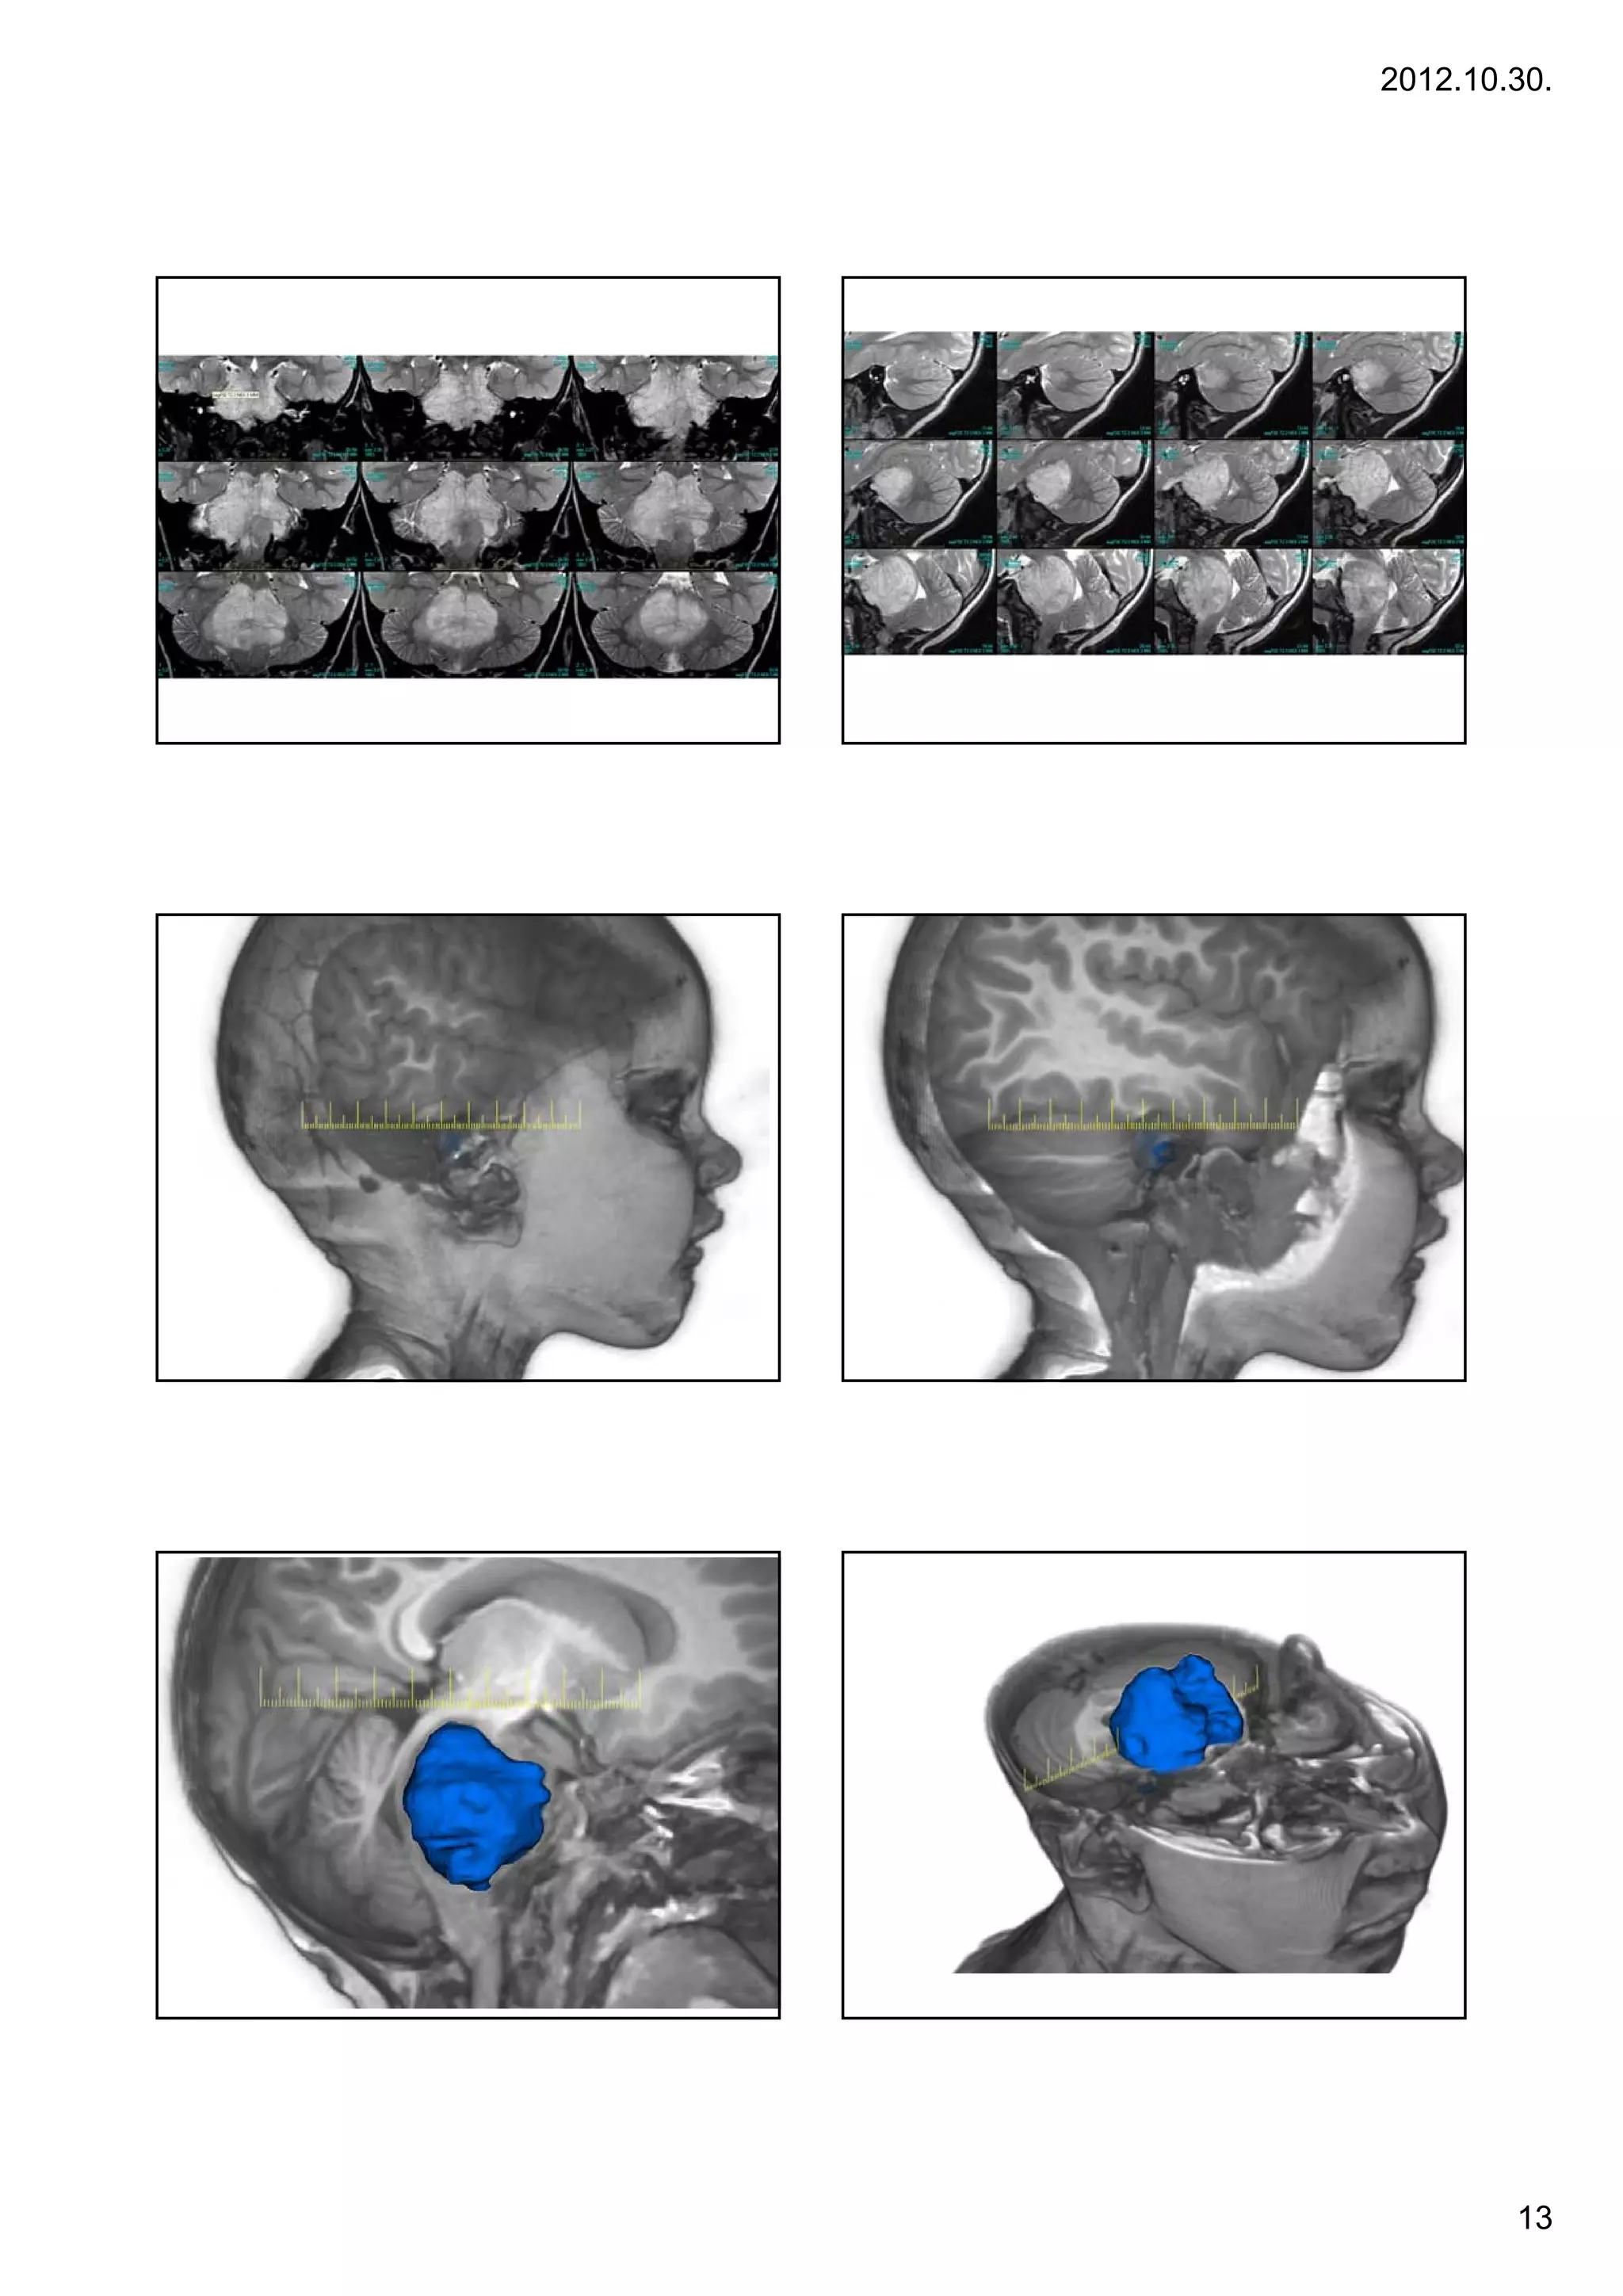

arise from the midbrain or medulla.                                                3 yr, F, ICP signs, cerebellum – tonsillar herniation

2012.10.30. 67 Case 1. 68 Case 1. Infant, generalized epileptic seizures. CT negative. Background: focal cortical dysplasia Case 2 2. Case 2. Pontine gliomas •Brain stem tumors account for 10 percent of pediatric brain tumors. The peak incidence is between ages 5 and 10. Pontine Gliomas - The patients' symptoms often improve dramatically during or after six weeks of irradiation. Unfortunately, problems usually recur after six to nine months, and progress rapidly. Survival past 12 to 14 months is uncommon, and new approaches to treating these tumors are urgently needed. Midbrain/Medullary Gliomas - With the use of radiation therapy, these patients often to well. Long-term survival ranges from 65 to 90 percent for brain stem tumors that arise from the midbrain or medulla. 3 yr, F, ICP signs, cerebellum – tonsillar herniation 12